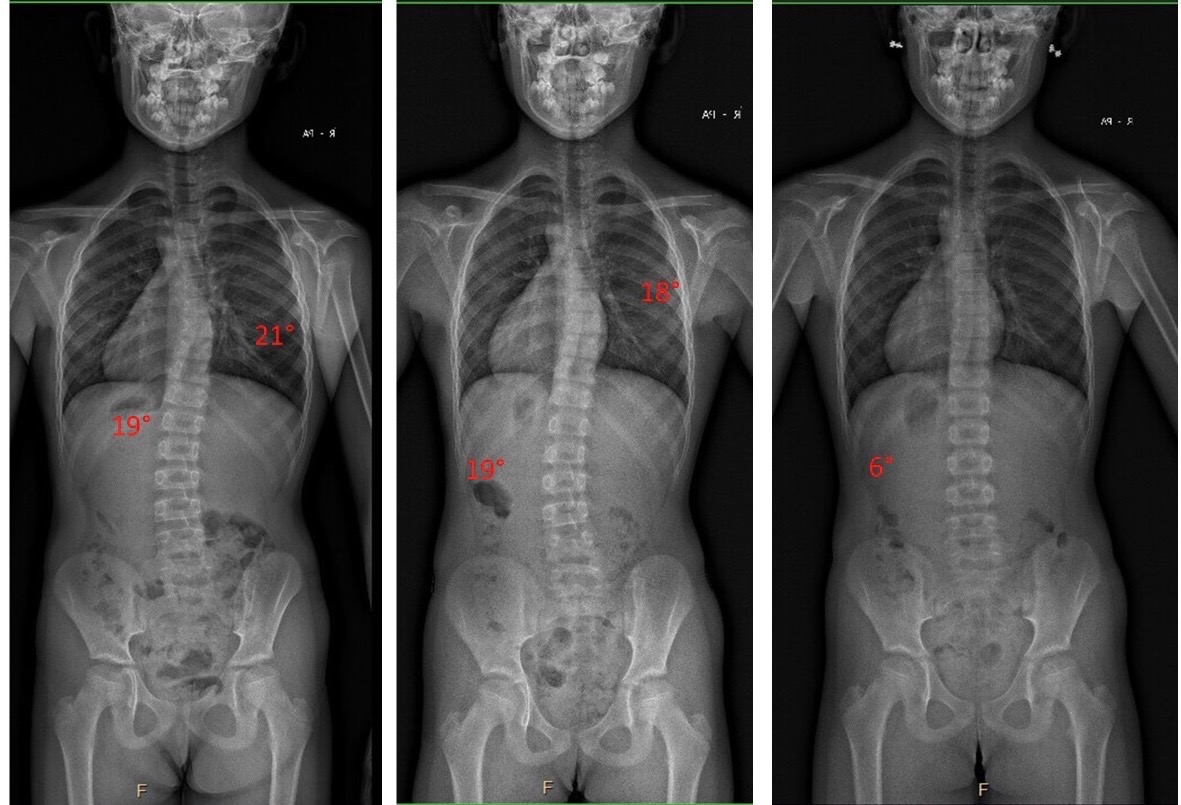

NAŠE VÝSLEDKY

Případová studie 2025

Případová studie 2021

Případová studie 2020